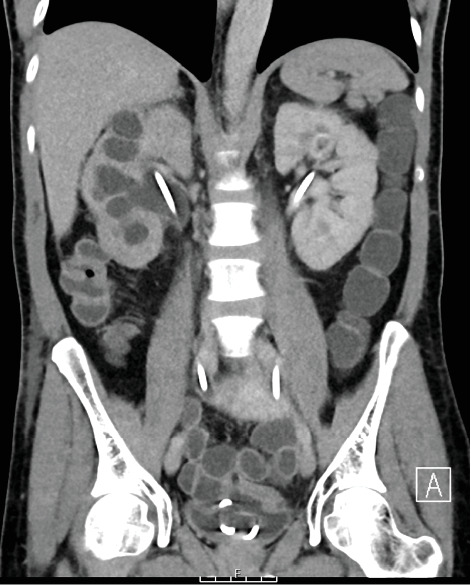

Background: Ureteric small bowel fistulas are rare entities, with limited reports in the literature. These pathological connections between the ureter and small bowel can lead to recurrent upper urinary tract infections and pose significant diagnostic and therapeutic challenges. The primary cause of ureteric small bowel fistula formation is iatrogenic intervention, such as percutaneous nephrolithotomy (PCNL) or abdominal surgery involving tissue resection. However, they can also arise spontaneously due to local chronic inflammation and infection. Given their rarity, there is no standardised management pathway, and the treatment approach should be individualised. Case Presentation: We present the case of a 57-year-old man presenting with a history of extensive locally advanced distal sigmoid carcinoma, managed with Hartmann's procedure with end colostomy followed by adjuvant radiotherapy and chemotherapy. He later developed a mid-ureteric small bowel fistula, presenting with urosepsis, a high-output stoma, deteriorating renal function and severe metabolic acidosis. Conservative management with regular ureteric stent exchanges every 3-4 months has successfully preserved renal function and improved his quality of life. Surgical closure was not pursued due to high operative risk, and repeat imaging has shown no evidence of persisting fistula, suggesting possible spontaneous closure. Conclusion: The treatment options for this ureteric small bowel fistula were limited. A lifelong nephrostomy was deemed unsuitable due to incompatibility with the patient's profession, and surgical intervention was associated with significant complexity due to the patient's history of malignancy and radiotherapy-related tissue changes. Therefore, a conservative strategy involving serial ureteric stent exchanges was pursued. Early recognition and individualised treatment of ureteric-enteric fistulas are essential, as timely intervention can significantly enhance prognosis and quality of life.

Abstract Image